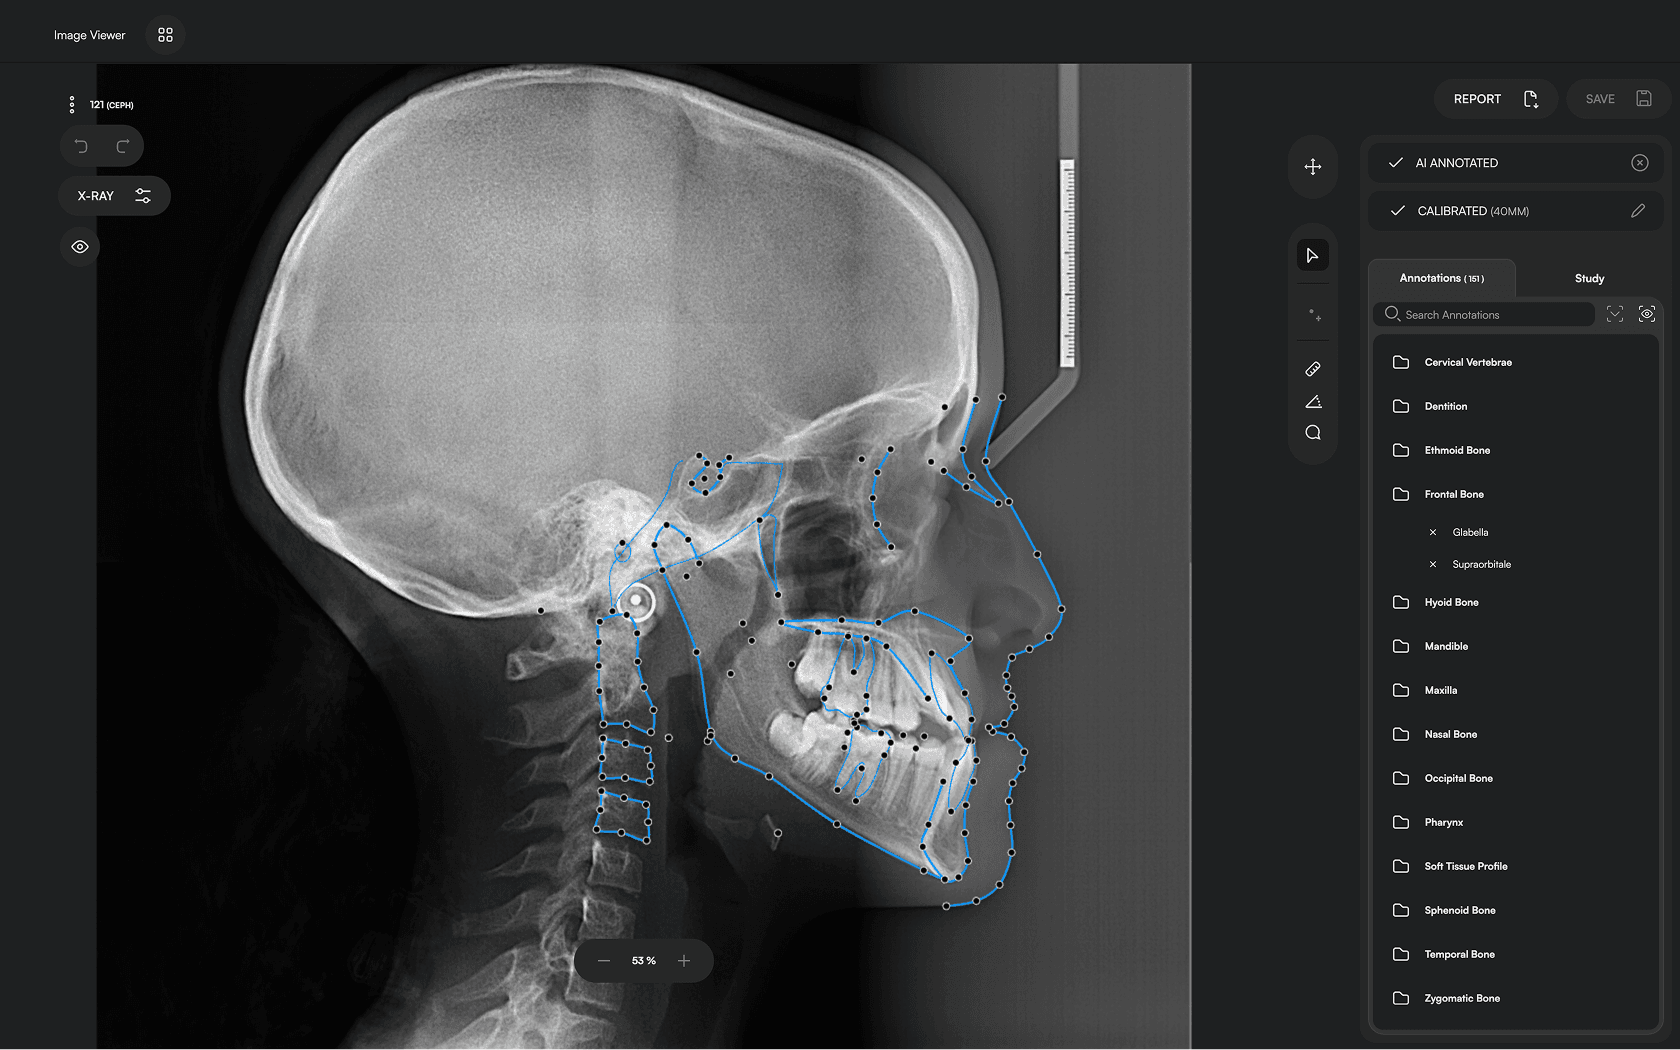

150+ landmarks traced in seconds

Identify 150+ orthodontic landmarks in under 10 seconds — a task that

traditionally may take more than 30 minutes.

Experience a comprehensive assessment of skeletal, dental, and soft tissue discrepancies.